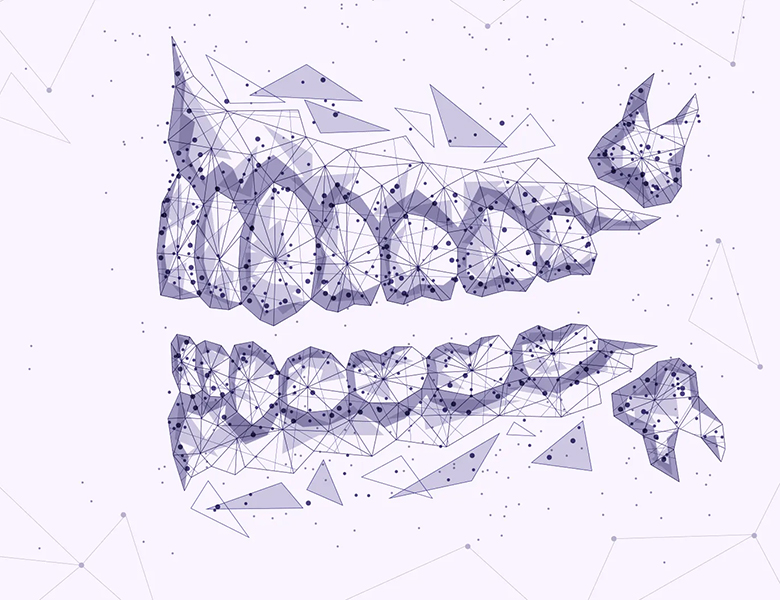

顎関節は、私たちが食事をし、話し、笑うために、一日に数千回も動かしている非常に複雑な関節です。

これらが複雑に絡み合うことで、顎の関節を支える「関節円板(クッション)」がずれたり、周囲の筋肉(咀嚼筋)が炎症を起こしたりします。

顎関節(耳の付け根あたり)の症状

顎関節症の診断において、最も核となる症状です。

関節の音(関節雑音)

口を動かすと「カクッ」「ポキッ」というクリック音や、ジャリジャリという砂を噛むような音がします。br>

これは関節内のクッション(関節円板)がずれて、骨と擦れているサインです。

口が開きにくい(開口障害)

指を縦に3本並べて入らない(約40mm以下)場合は注意が必要です。br>

朝起きたときに突然開かなくなる「クローズド・ロック」という状態になることもあります